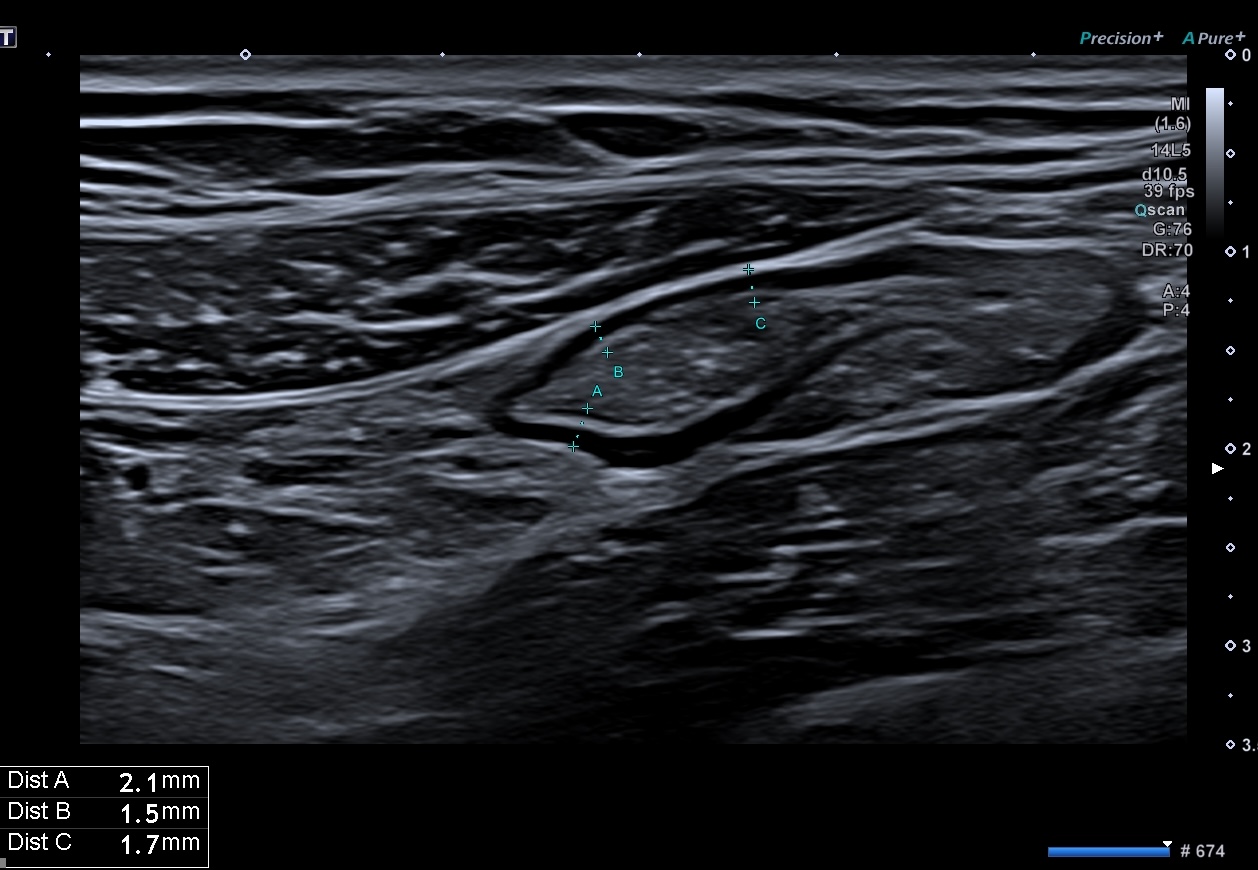

Dès J7 l’amélioration échographique de la paroi se poursuit. L’épaisseur pariétale approche la normale (3 mm) et par endroit 2,1 mm, les couches sont bien visibles, le doppler reste intense (Limberg 3) .

le score de Milan, segment le plus atteint est de (3 x1,4 +2) MUC = 6,2

la maladie reste active, mais la réponse est impressionnante et se poursuit.